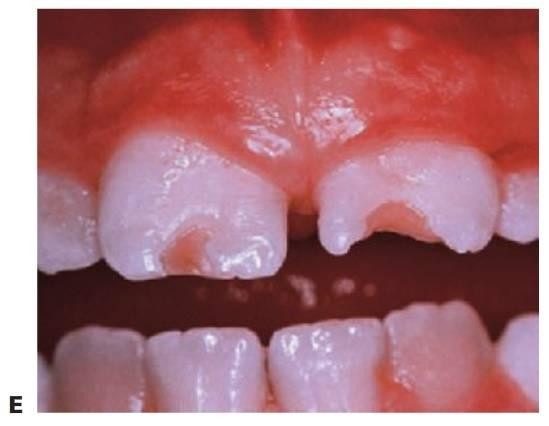

Fractura o fisura incompleta del esmalte sin pérdida de estructura dental. Las fracturas no cruzan la unión amelodentinaria y, por lo general, requieren transiluminación o luz indirecta para poder visualizarse (fig. 7.6).

Fracturas adamantinas y amelodentinarias no complicadas

Las fracturas no complicadas se limitan al esmalte o al esmalte y la dentina, pero no afectan a la pulpa. La presentación más habitual es una fractura oblicua de los ángulos mesial o distal de un incisivo.